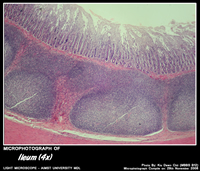

ILEUM

Histology of Ileum

• Has fewer villi,

• Very short broad tipped ( club shaped )

• Relatively abundant goblet cells.

• Lamina propria typically contains many lymphoid nodule clusters (Peyer’s patches).

• Bulge into luminal surface and extend into the luminal mucosa.